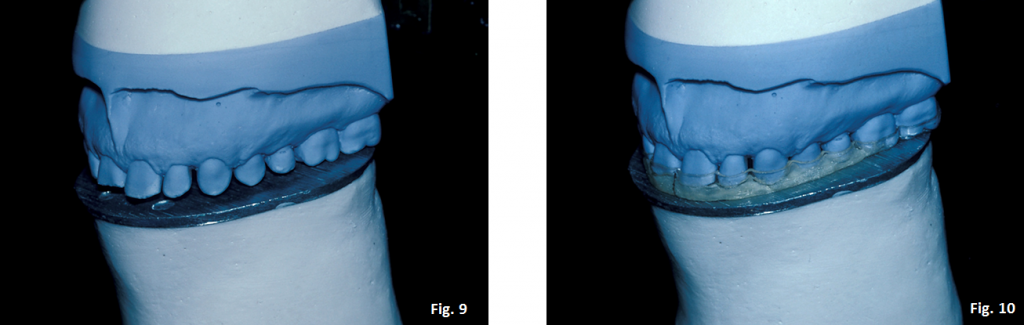

The instructions to the technician are to wax the incisal edges and buccal cusp tips of the maxillary arch to touch the flat plane (a natural Curve of Spee can be added to the distal buccal cusp of the first molar and in the second molar region). (Figs. 9-10)